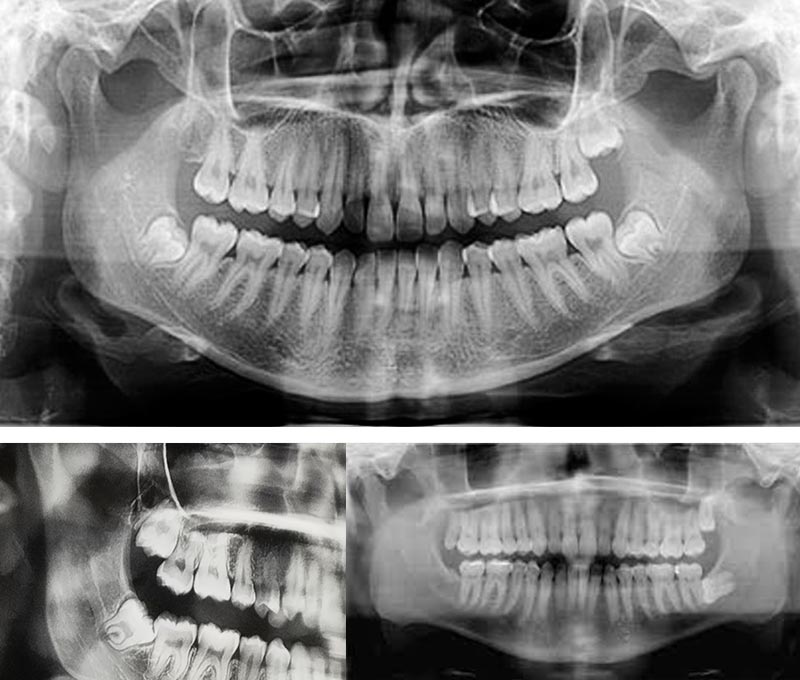

Výstupní komprimovaný formát JPG u panoramatických nebo kafalometrických snímků je stále velmi kvalitní a je možné ho bez obav dále zpracovávat v různých grafických editorech. Zvětšení panoramatického snímku je 1,25-1,5 a u kefalometrického snímku 1,13 konstantně.

FOV pro jednotlivé zuby: průměr válce 50 mm x výška 50 mm (nebo 50mm x 80mm) FOV pro skupinu zubů: průměr válce 80 mm x výška 80mm FOV dvojitý sken – průměr válce 2 x 80 mm x výška 80 mm (nebo 2x 80 mm x 50 mm) FOV trojitý sken – průměr válce 3 x 80 mm x výška 80 mm (nebo 3x 80 mm x 50 mm,

Rozlišení: (velikost voxelu)

Nízké – 400µm

Normální – 200µm

HD rozlišení – 100µm

Endodoncie – 75µm

Zvětšení: 3D 1,38 / 1,44 / 1,8